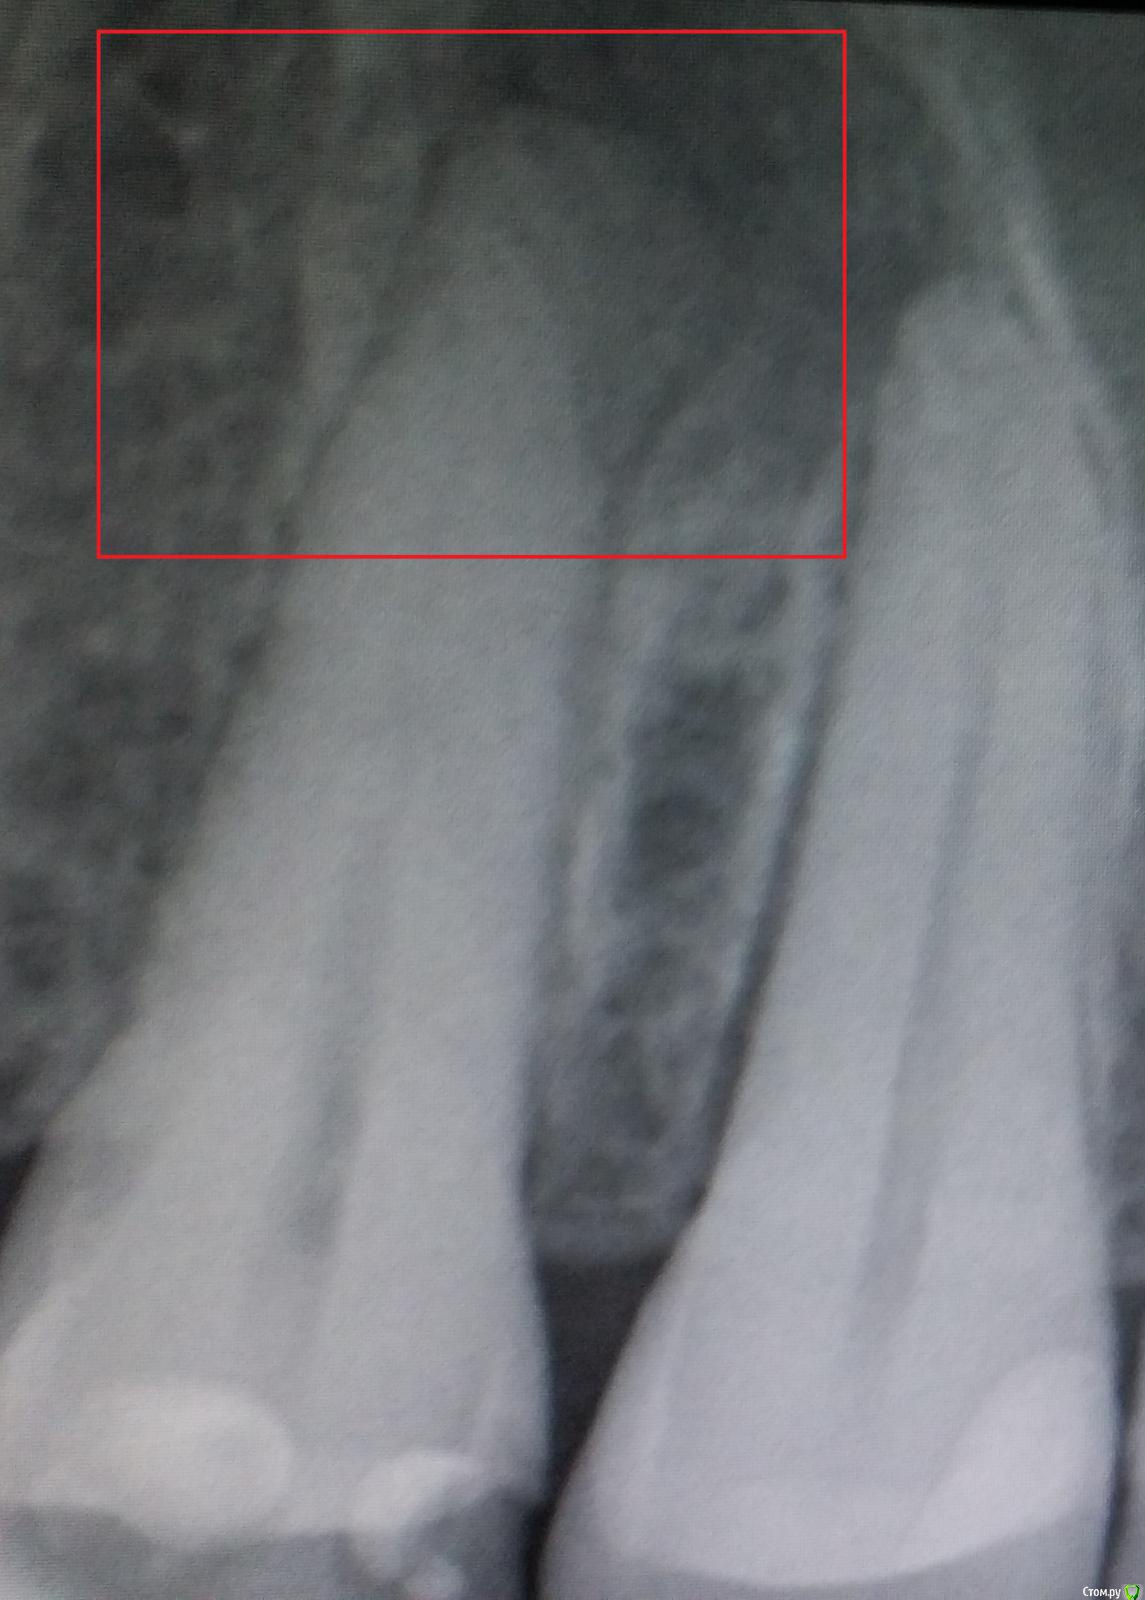

Гость ahv Опубликовано 9 ноября, 2015 Поделиться Опубликовано 9 ноября, 2015 Добрый день! На снимке выделена область, что это? Не болит. Был периодонтит соседнего, лечат. Ссылка на комментарий

red_butler Опубликовано 10 ноября, 2015 Поделиться Опубликовано 10 ноября, 2015 Это не онНе важно если я ошибся с групповой принадлежностью зуба, зуб на снимке рядом с леченным, нужно эндодонтически лечить 2 1 Ссылка на комментарий